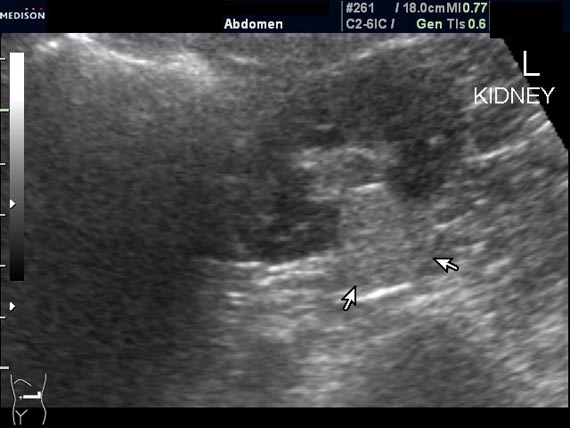

Случайная находка в нижней трети левой почки (не в полюсе, а по задне-медиальной поверхности).

Образование в левой почке

ПО УЗ-семиотике образование соответствует ангиомиолипоме (AML). По правилам в таких случаях необходимо выполнить КТ, доказать преимущественно жировой состав опухоли, затем проводить УЗ-наблюдение.

Согласен. Именно с таким диагнозом (ангиомиолипома) отправил на КТ. Особенностью случая ИМХО является заметный "выход" образования за контур почки (на 2/3 объема).

При ультрасонографии ангиомиолипома выглядит как округлое образование без капсулы с однородной внутренней эхоструктурой и четкими контурами; эхогенность ее чаще всего равна или чуть выше эхогенности перинефральной клетчатки [7]. Значительно реже эхогенность ангиомиолипом может быть равна эхогенности почечной паренхимы; такие опухоли состоят почти полностью из гладкомышечной ткани [8]. Иногда позади ангиомиолипомы может определяться слабая акустическая тень.